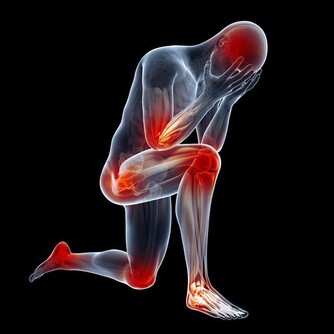

1、腹脹、腹痛。原因是由於腸道功能紊亂,或者腸道梗阻而致。

部位多集中在中下腹部,多為隱痛或脹痛,還有漸漸加重的趨勢。

3、貧血,當長期慢性失血,超過機體造血的代償功能時,

病人即可出現貧血這種,大腸癌的早期症狀。